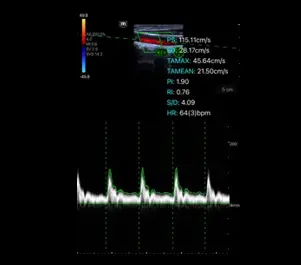

PW Auto Calc

Aвтоматично PW трасиране и калкулации на PS, ED, TAMAX, TAMEAN, RI, PI, S/D, HR